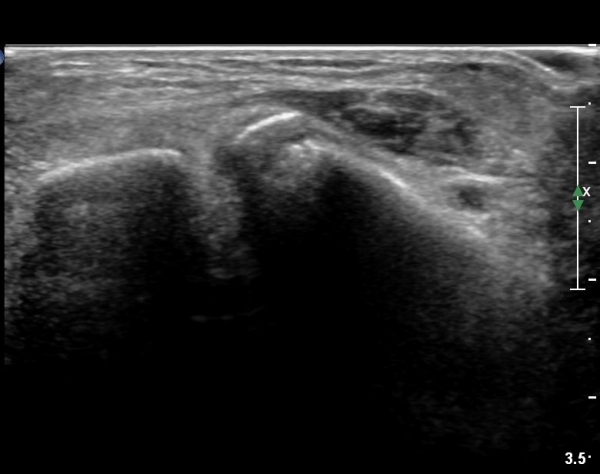

[¹ß¸ñ] distal tibiofibular ligament sprain with avulsion fracture of tibia

she revealed limping gait. on examination, there is swelling around ankle with limited ankle motion, localized tenderness at distal tibiofibular ligament and ATF ligament.

ÃÊÀ½ÆÄ °Ë»ç